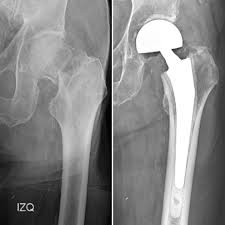

Cirugía de Cadera.

El Dr. Mauro Andreoli es un especialista en ortopedia y traumatología con amplia experiencia en cirugía de cadera, destacándose en técnicas mínimamente invasivas. Es ex residente del Hospital Italiano de Buenos Aires y ex fellow en patología de cadera en la misma institución.

Actualmente, forma parte del staff del Sanatorio San Gerónimo en Santa Fe. Su enfoque profesional está orientado al tratamiento de enfermedades y lesiones de cadera, utilizando métodos avanzados y procedimientos modernos para garantizar una recuperación eficiente.

• Especialista Cadera y Rodilla - ACARO/Prótesis de Cadera.

• Cirugía Mini Open (Minimamente invasiva.